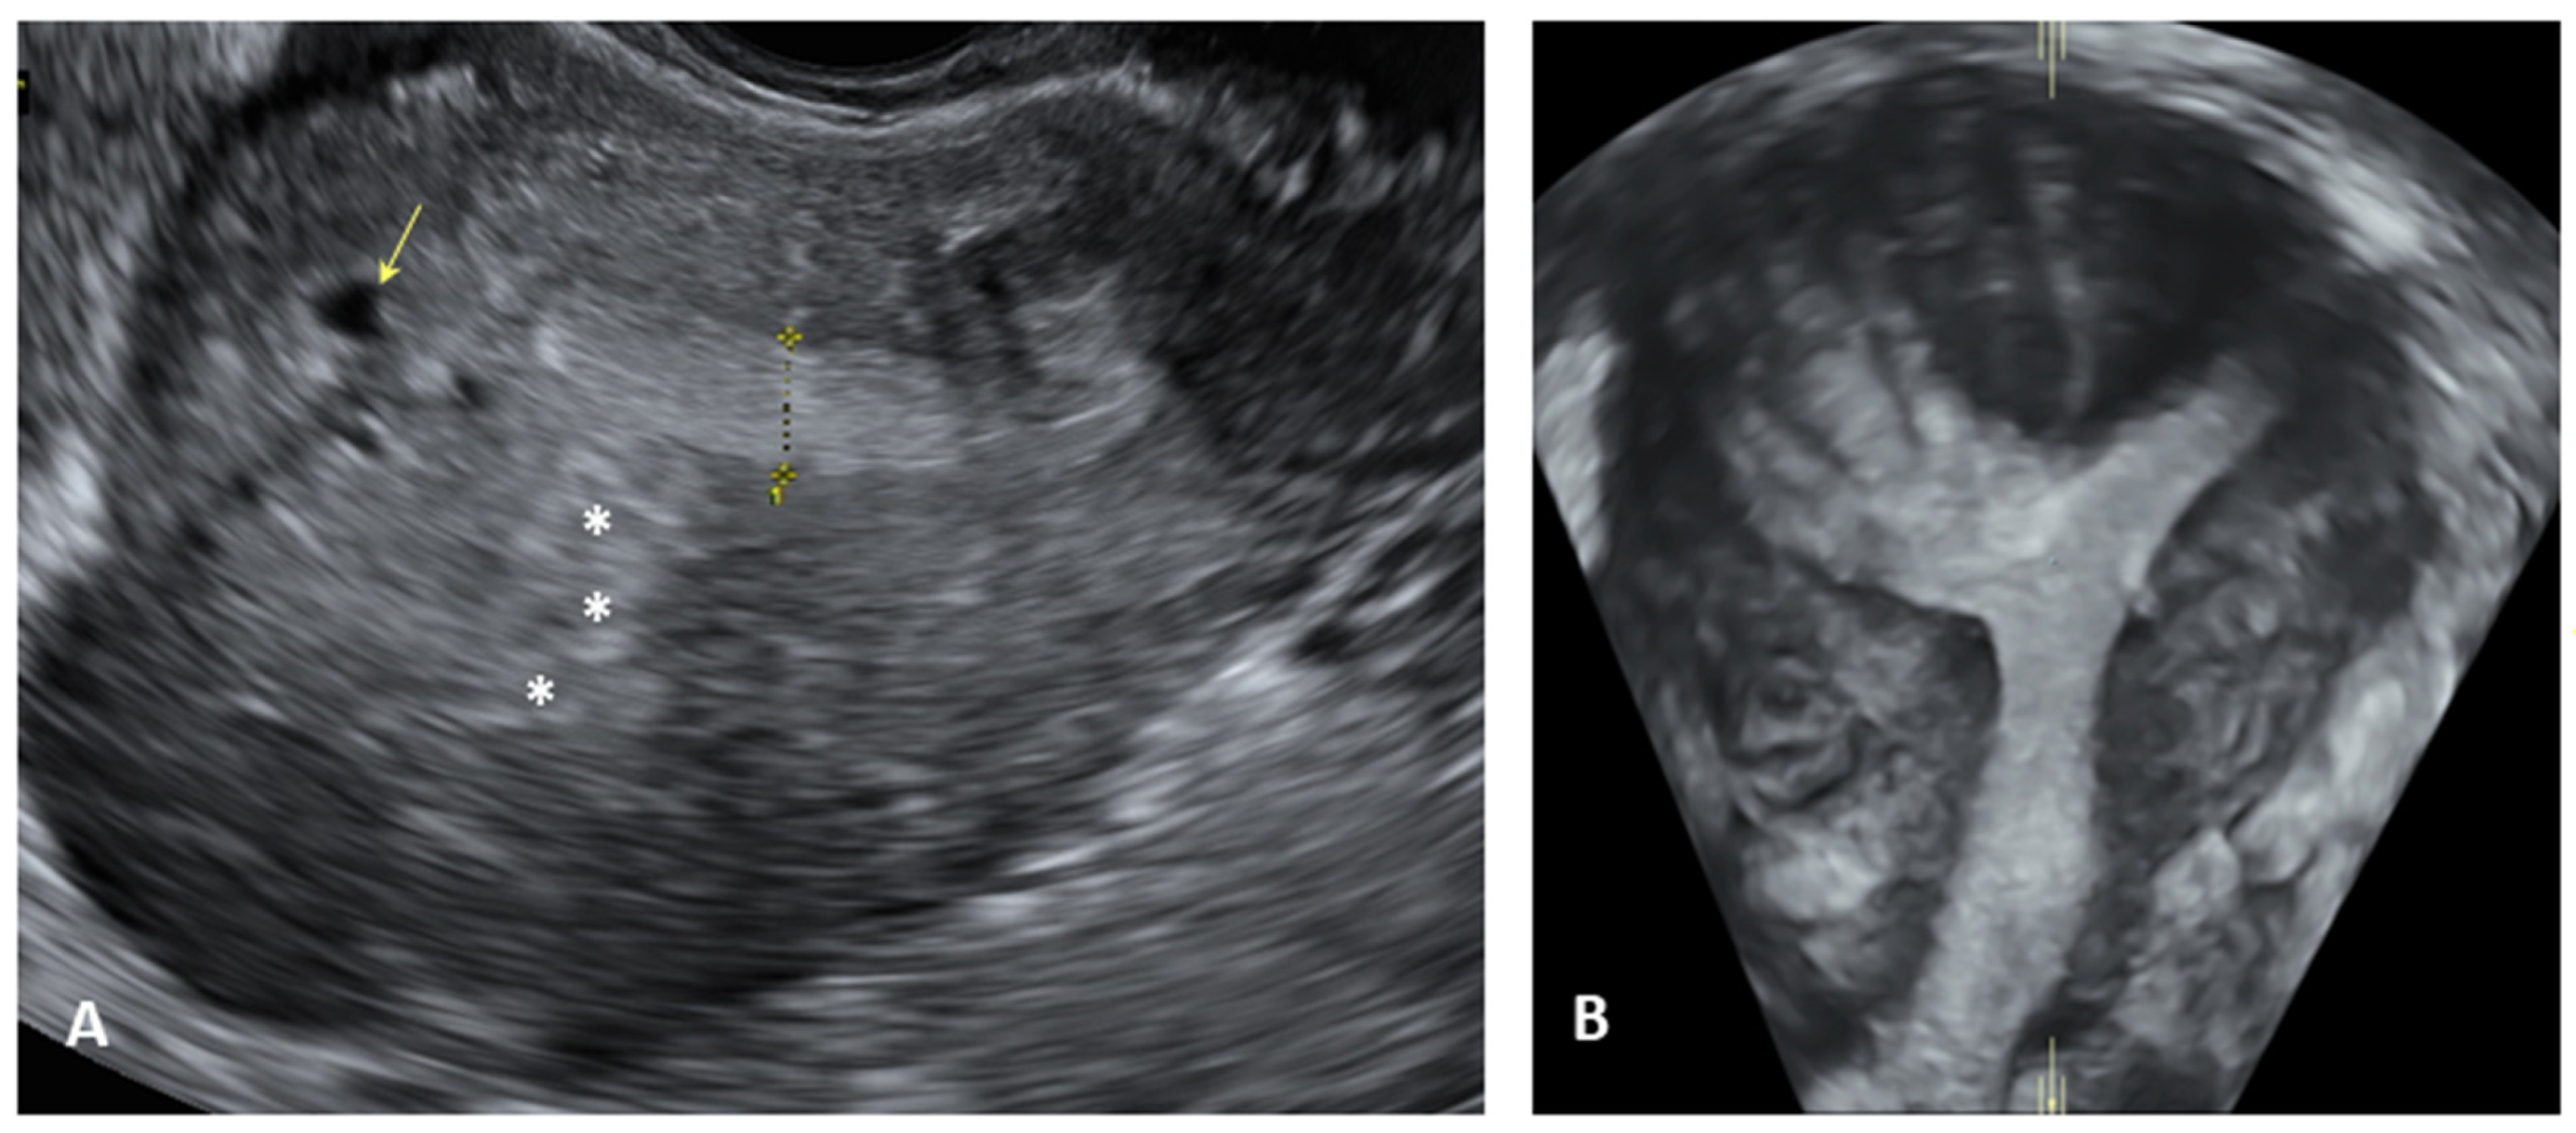

- Guerriero, S.; Condous, G.; van den Bosch, T.; Valentin, L.; Leone, F.P.; Van Schoubroeck, D.; Exacoustos, C.; Installé, A.J.; Martins, W.P.; Abrao, M.S.; et al. Systematic approach to sonographic evaluation of the pelvis in women with suspected endometriosis, including terms, definitions and measurements: A consensus opinion from the International Deep Endo-metriosis Analysis (IDEA) group. Ultrasound Obstet. Gynecol. 2016, 48, 318–332. [Google Scholar] [CrossRef]

- Martire, F.G.; Russo, C.; Selntigia, A.; Nocita, E.; Soreca, G.; Lazzeri, L.; Zupi, E.; Exacoustos, C. Early noninvasive diagnosis of endometriosis: Dysmenorrhea and specific ultrasound findings are important indicators in young women. Fertil. Steril. 2022, 119, 455–464. [Google Scholar] [CrossRef]

- Exacoustos, C.; Lazzeri, L.; Martire, F.G.; Russo, C.; Martone, S.; Centini, G.; Piccione, E.; Zupi, E. Ultrasound Findings of Adenomyosis in Adolescents: Type and Grade of the Disease. J. Minim. Invasive Gynecol. 2021, 29, 291–299.e1. [Google Scholar] [CrossRef] [PubMed]